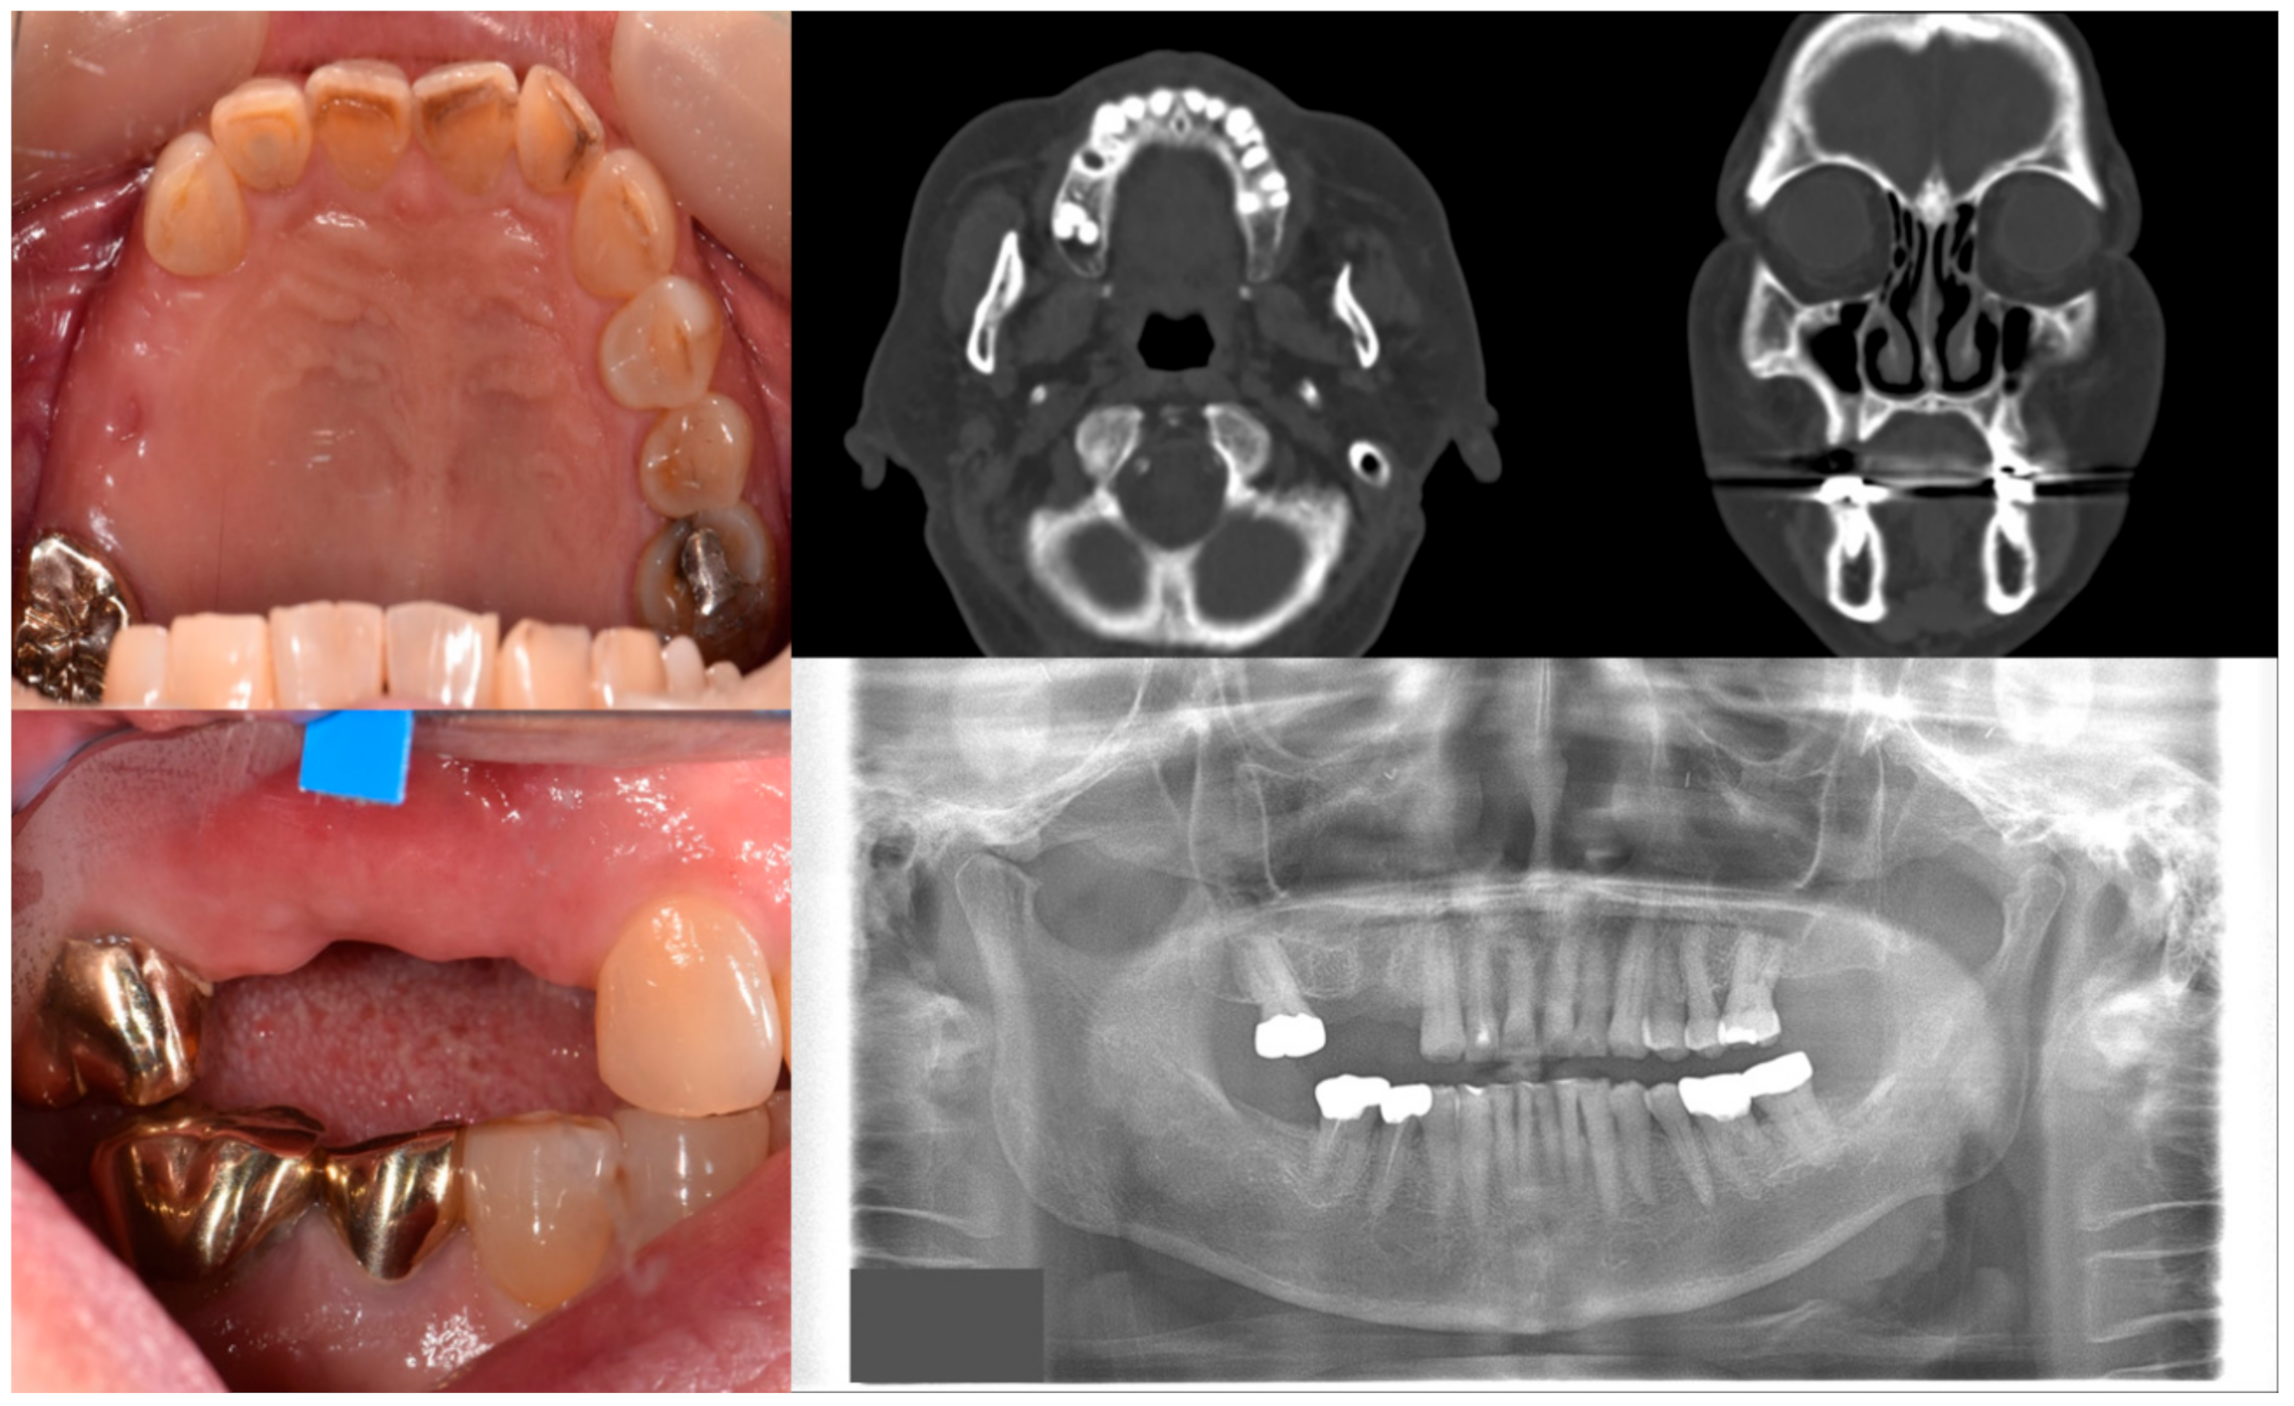

Figure 1.

Case 1 with MRONJ Stage 0: Clinical photos, panoramic view, and computed tomography imaging showing non-significant findings on the maxillary right posterior area. An 81-year-old female patient with a history of taking oral alendronate for five years complained of pain after removing the right upper second premolar five months before. There were no specific findings other than slight soft tissue depression in the area and hard tissue defect presumed to be an extraction socket.